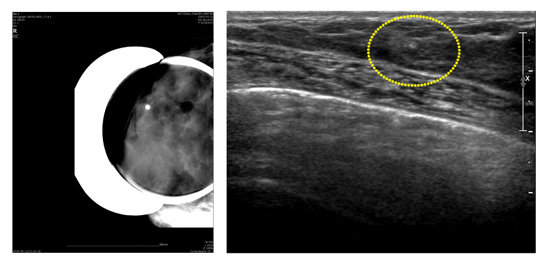

맘모톰 조직 검사는 조직을 확보하는데 어려움이 있었던 기존의 방법을 개선한 검사법입니다. 기존의 방법과 달리 병소에 바늘을 한번 위치시킨 후 반복적으로 여러 번 원하는 양의 조직을 얻을 수 있으며 수술 조직검사만큼 정확합니다.

영상 유도 하에 굵은 바늘(11 또는 8게이지)을 병소에 넣고 진공 흡입기를 작동하여 바늘 안으로 조직을 끌어들인 후 바늘 내부의 회전칼을 작동시켜 자동으로 병변을 잘라 유방 밖으로 배출해주는 최신 조직검사 방법입니다. 암이 의심되는 경우는 조직 검사 목적으로 이용되지만, 병변이 최대 직경 3cm이하의 양성 종양으로 병소를 제거하기를 원하는 경우에는 큰 흉터 없이 그 병변을 완전히 제거할 수 있어 양성 종양의 치료목적으로 사용됩니다.

그러나 암으로 강력히 의심되는 병변을 맘모톰으로 제거하는 것은 바람직하지 않습니다. 그 이유는 암 조직을 무리하게 제거하다 보면 병변 부위에 출혈이 많아지거나 딱딱해지며, 특히 유방보존수술을 할 때는 깨끗한 절단면을 찾을 수 없고 수술 범위를 정하는데 어려움이 생길 수 있기 때문입니다.

[ 맘모톰 조직검사 ]

[ 맘모톰 조직 검사 맘모그램 사진과 맘모톰 조직 검사 초음파 사진 ]